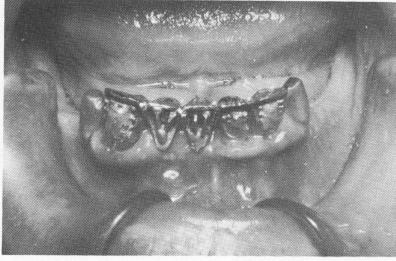

Fig. 12-58. During the healing of the soft tissues after the first surgical stage, the castings are fitted over the remaining abutment teeth with the politics soldered to the rest of the framework.